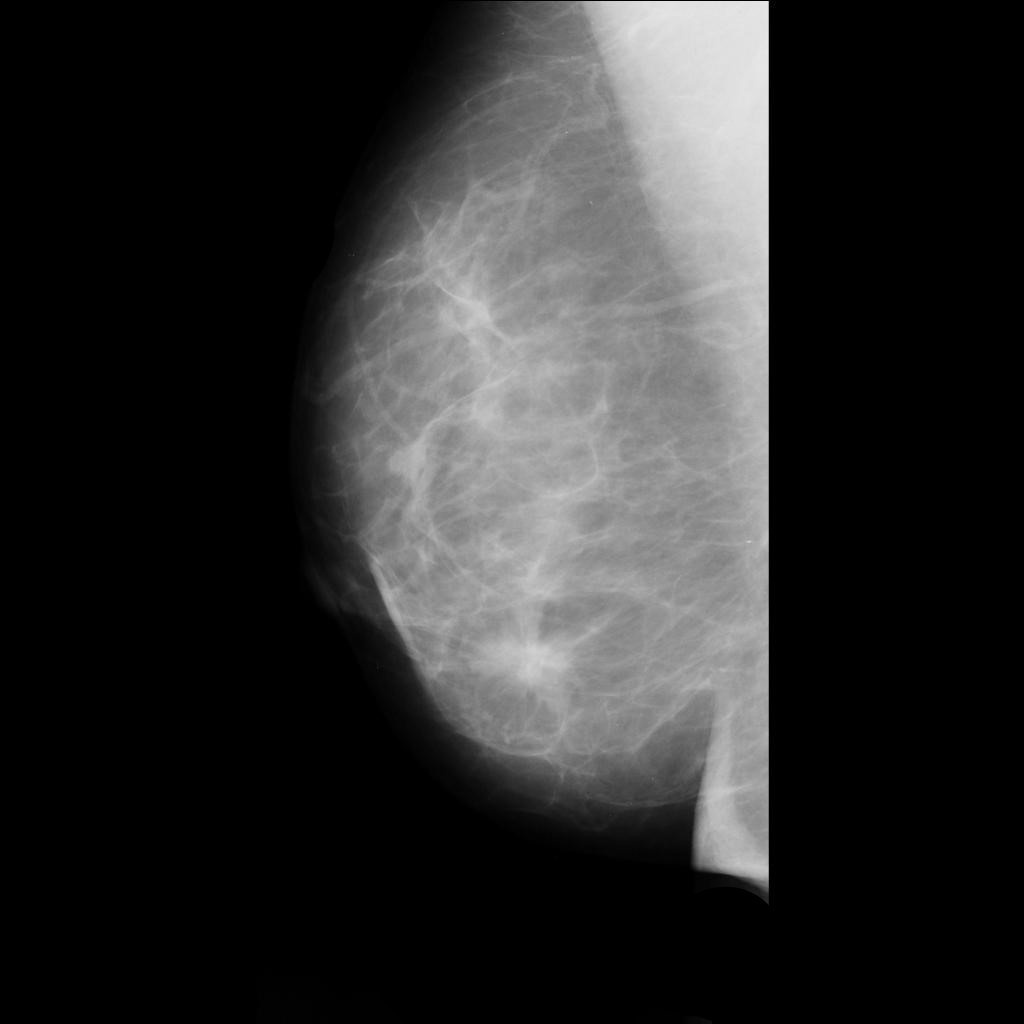

benign